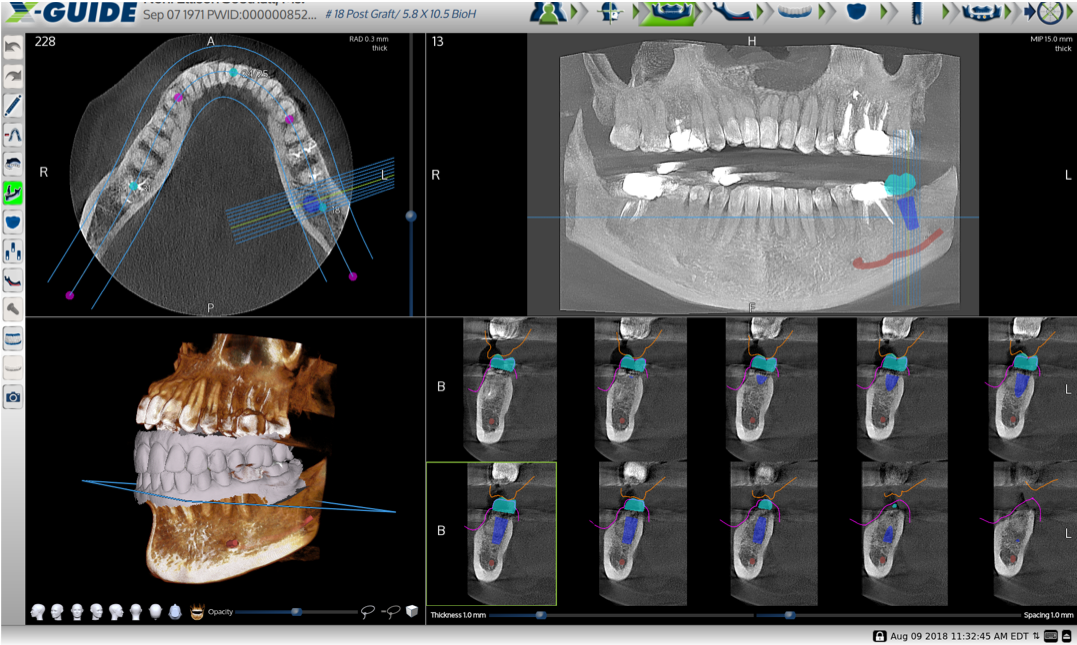

Computer-guided surgery has been validated since the introduction of digital technology in the early 2000s as an efficient and reliable technique for obtaining functional and esthetic outcomes (Figure 4).28,29 Computer-guided implant surgery is defined by the use of a surgical template that reproduces a virtual implant position designed from digital data.30 If a dentist is using a static surgical guide, it can be created with the use of 3D printing.31 CAD/CAM software is an essential tool because it is responsible for guiding robotic devices that design objects and assemblies in a virtual environment.32 CAD/CAM machines can be used to manufacture ceramic restorations based on computer-assisted design and produce a restoration at a single dental appointment, an increasingly popular process.33Dentists can directly scan prosthetic preparations or scan bodies, import those scans into a CAD program, design the restoration, and mill them in an esthetic material.34,35 The restorations are then delivered to the patient through what has been a succinct digital workflow.

Fig 4. Dynamic guided implant treatment-planning panoramic with intraoral scan imported, allowing treatment planning with occlusion between arches.

Figure 4